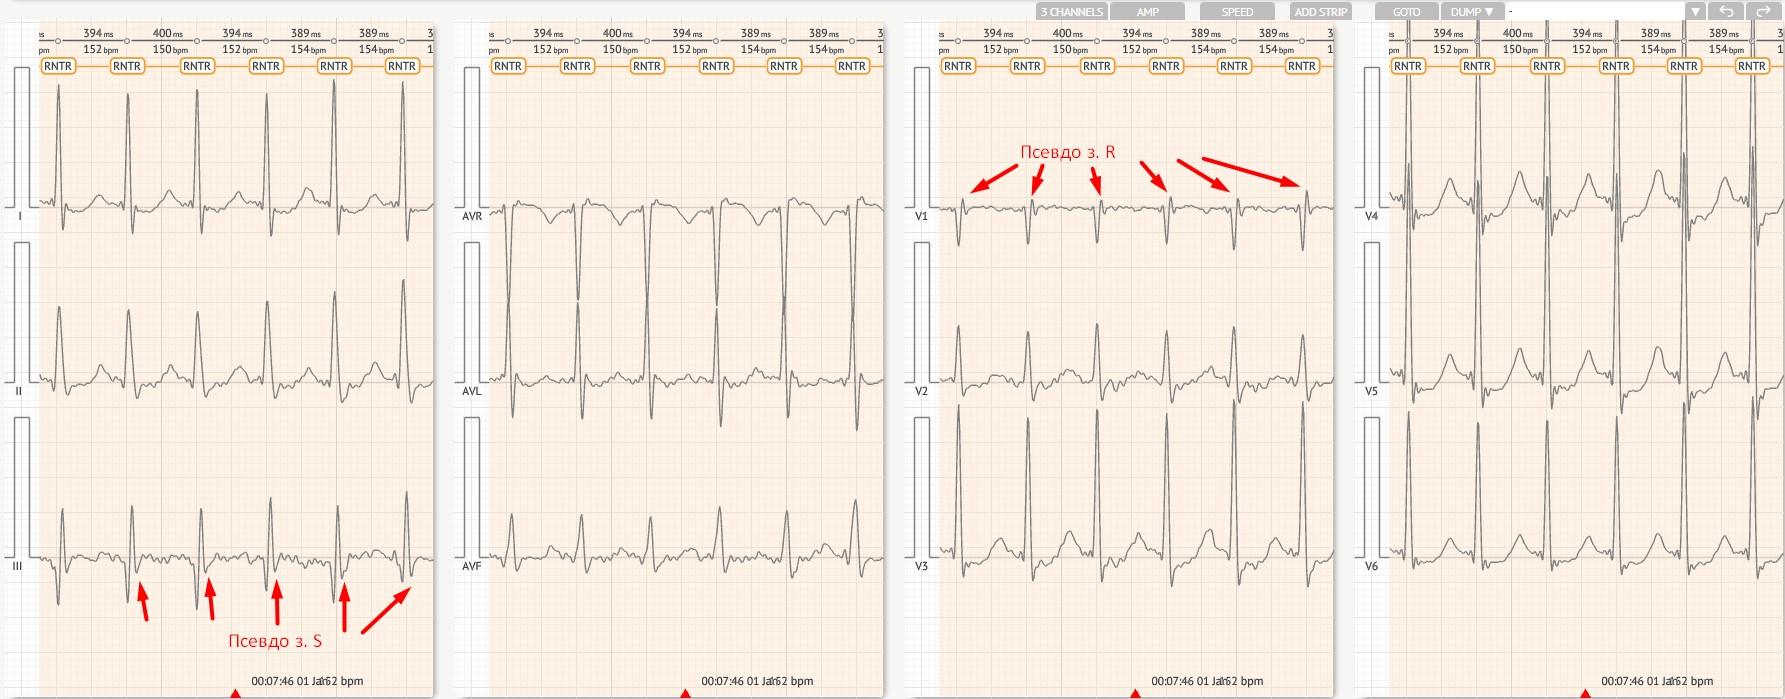

Reentrant AV Nodal Tachycardia - (RNTR)

Definīcija

Reentranta tahikardija AV mezglā vai ap to (tipiskas vai netipiskas formas).

Tipisks (ortodromisks, lēni-ātri) (80%)

Stingri regulārs R-R, 140–250 sitieni minūtē.

Normāls QRS (ja vien nav novirzes).

P vilnis bieži ir slēpts vai atrodas QRS kompleksa tuvumā; R-P \< 90 ms.

Nav iepriekšējas ierosmes sinusa sitienos.

Netipisks (antidromisks, ātri-lēni) (20%)

Retrogrādais P vilnis, kas parādās pēc QRS kompleksa.

R-P > 90 ms, bet joprojām \< P-R.